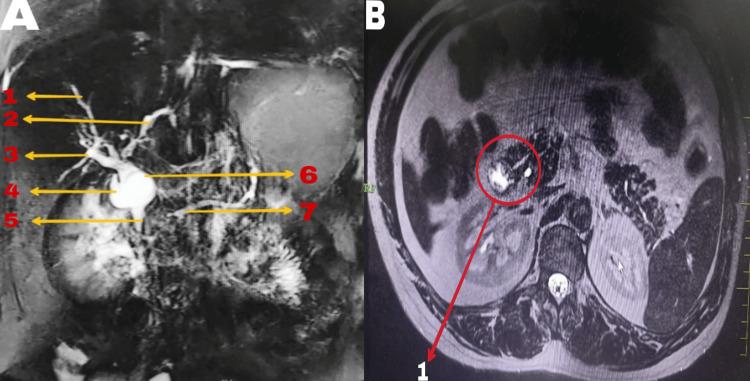

Choledochal cysts (CCs) are quite rare and are characterized by anomalous dilations of the biliary tree, mostly due to anomalous pancreaticobiliary junction (APBJ). A less frequent congenital anomaly due to incomplete fusion of pancreatic ducts, pancreas divisum (PD) can complicate the clinical course of CC. Although rare, the coexistence of CC and PD presents significant clinical challenges. With very few documented cases globally, our experience with this case adds to our understanding of this unique condition. This report aims to highlight the complex relationship between these anomalies and underscores the need for heightened clinical awareness and comprehensive management strategies to improve patient outcomes. We present the case of a 27-year-old female patient who was diagnosed with type 1 CC with concomitant PD after recurrent pancreatitis and multiple biliary interventions. Her choledochal cyst was excised with Roux-en-Y hepaticojejunostomy (RYHJ). Histopathological examination confirmed CC with evidence of chronic inflammatory changes but no malignancy. The preoperative hospital stay was three days with an operative duration of 150 minutes and intraoperative blood loss of 210 mL. Postoperatively, the patient was discharged on day 5. The pain score as per the Visual Analog Scale (VAS) was 2 on the day of discharge. The patient was started on diet on postoperative day (POD) 3. The abdominal drains were removed on POD 4 (subhepatic) and POD 5 (pelvic). Sutures were removed on POD 10, with follow-up for two years with no recurrence of similar complaints. This case illustrates the diagnostic challenge of synchronous CC and PD and elaborates on the role of extensive imaging modalities in guiding management decisions. The surgical approach remains the foremost for CC; preventing complications in the form of cholangitis and malignancy is the mainstay of treatment. The present report is an addition to the existing literature on the management of complex biliary anomalies and places special emphasis on the need for a multidisciplinary approach with individualized treatment strategies in such rare clinical scenarios. Further studies are required to clarify pathophysiological mechanisms linking CC and PD, with the need for better therapeutic strategies toward the optimization of patient outcomes. More studies with robust data are necessary to draw better conclusions.

胆总管囊肿(CCs)相当罕见,其特征是胆管树异常扩张,主要原因是胰胆管异常汇合(APBJ)。胰腺分裂(PD)是一种因胰腺导管不完全融合导致的不太常见的先天性异常,可使CC的临床病程复杂化。尽管罕见,但CC和PD并存带来了重大的临床挑战。全球记录在案的病例极少,我们对该病例的经验增进了我们对这种独特情况的了解。本报告旨在突出这些异常之间的复杂关系,并强调提高临床意识和制定综合管理策略以改善患者预后的必要性。我们报告一例27岁女性患者,该患者在反复胰腺炎发作和多次胆道干预后被诊断为1型CC合并PD。她的胆总管囊肿通过 Roux-en-Y 肝空肠吻合术(RYHJ)切除。组织病理学检查证实为CC,有慢性炎症改变的证据,但无恶性病变。术前住院3天,手术时间150分钟,术中失血210毫升。术后,患者于第5天出院。出院当天视觉模拟量表(VAS)疼痛评分为2分。患者术后第3天开始进食。腹腔引流管分别于术后第4天(肝下)和第5天(盆腔)拔除。缝线于术后第10天拆除,随访两年无类似症状复发。该病例说明了同步存在CC和PD的诊断挑战,并阐述了广泛的影像学检查在指导管理决策中的作用。手术方法仍然是CC治疗的首要方法;预防胆管炎和恶性肿瘤等并发症是治疗的主要手段。本报告是对复杂胆道异常管理现有文献的补充,并特别强调在这种罕见临床情况下采用多学科方法和个体化治疗策略的必要性。需要进一步研究以阐明连接CC和PD的病理生理机制,需要更好的治疗策略来优化患者预后。需要更多有可靠数据的研究才能得出更好的结论。